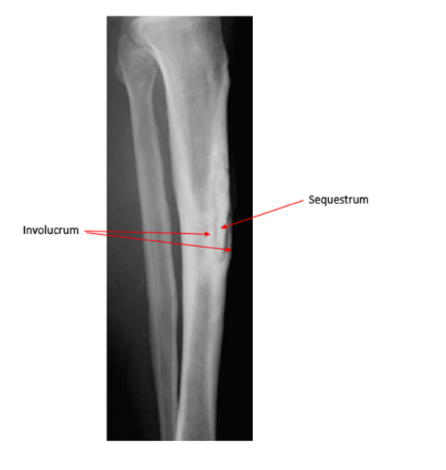

Chronic Osteomyelitis

Identify